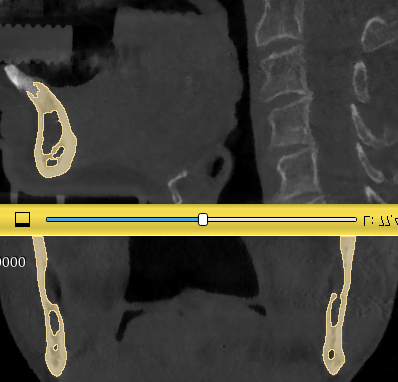

When I use dental segmentator module on CBCT, some gaps are still left inside the jaw bones. What is the easiest way to fill in that empty space.

You can use the Paint Effect in Segment Editor module, setting an Editable Intensity Range, Inside All Visible Segments.

Also, you can set a Threshold that fill the gaps, so you can know the pixel value of the area you want to to fill, and set the Use For Masking from there, that will automatically create the Editable Intensity Range.